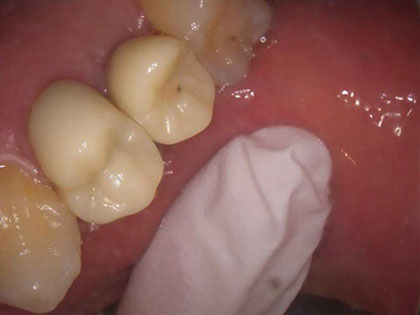

• インプラント治療完了時2